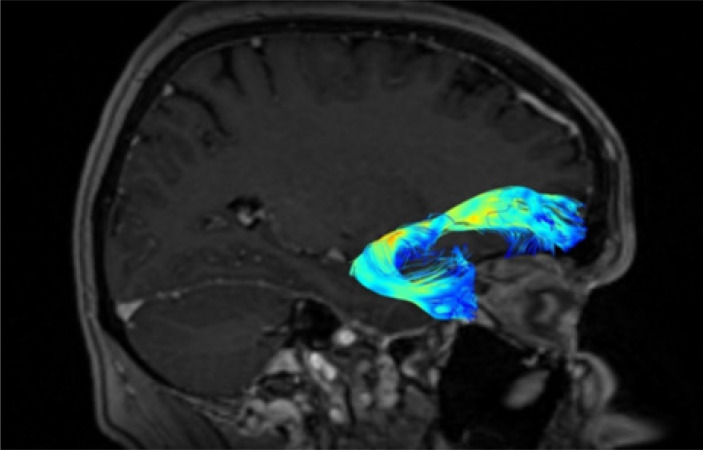

Diffusion tensor imaging (DTI) and tractography are powerful non-invasive techniques for studying the human brain's white matter pathways. The uncinate fasciculus (UF) is a key frontotemporal tract involved in emotion regulation, memory, and language. Despite advancements, challenges persist in accurately mapping its structure and function due to methodological limitations in data acquisition and analysis. This review aims to provide a comprehensive overview of the strengths and limitations of DTI and tractography in studying the UF, focusing on its anatomy, data acquisition techniques, and associated neurological and psychiatric disorders. A systematic review of over 30 years of literature on UF was conducted, encompassing anatomical studies, DTI methodologies, and clinical applications. Studies involving both postmortem dissections and in vivo imaging were analysed, with particular attention to different DTI acquisition parameters, fibre tracking algorithms, and their impact on imaging accuracy. DTI has significantly improved our understanding of UF anatomy and its role in neurocognitive functions. However, methodological constraints such as low spatial resolution, crossing fibres, and inter-subject variability limit its precision. Advances in higher-field magnetic resonance imaging, improved diffusion models, and artificial intelligence-enhanced tractography offer promising solutions. UF abnormalities have been linked to various disorders, including schizophrenia, depression, autism spectrum disorders, and neurodegenerative diseases. While DTI and tractography are invaluable tools for studying the UF, their limitations necessitate cautious interpretation of results. Future research should focus on refining imaging techniques to enhance accuracy and clinical applicability, paving the way for better diagnostic and therapeutic strategies.